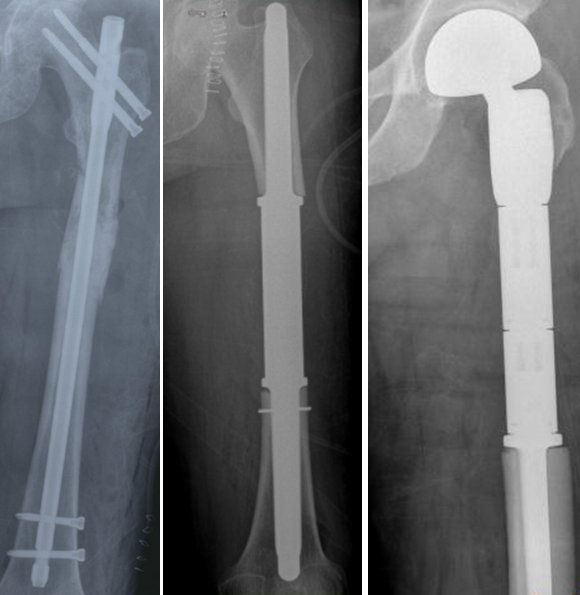

What we have described so far were lesions originating primarily from the bone or soft tissue itself. Metastases, on the other hand, are malignant cells separated from a cancerous tissue (eg lung cancer, breast cancer, kidney cancer or prostate cancer) in the body, coming to the bones through the blood and causing a mass there. Metastases are generally disorders of the middle-aged group. Here, the patient already knows that he has cancer to a large extent or is receiving cancer treatment. For example, hip, leg, shoulder, elbow or low back pain that has started recently in a patient known to have lung cancer suggests that metastasis has occurred in the foreground (image-24). Metastases are rapidly progressive malignant lesions. Treatment should be done quickly. Otherwise, severe bone pains will occur and eventually pathological fracture will be inevitable. In this case, treatment will become more difficult.

Pic 25

Radiotherapy or surgical treatment is at the forefront in the treatment of bone metastases. If the patient does not have a pathological fracture or a pathological fracture threat, radiotherapy alone may be sufficient. However, if a pathological fracture has developed or is about to develop (pathological fracture threat), surgery should be performed. The aim is to relieve the patient's pain and bring him back to life by regaining his daily activities as soon as possible. In the operation, the tumorous area is removed and the resulting bone defect is removed by using an implant (pic-25). Sometimes the patient's pain does not go away despite radiotherapy. In this case, surgery comes to the fore.